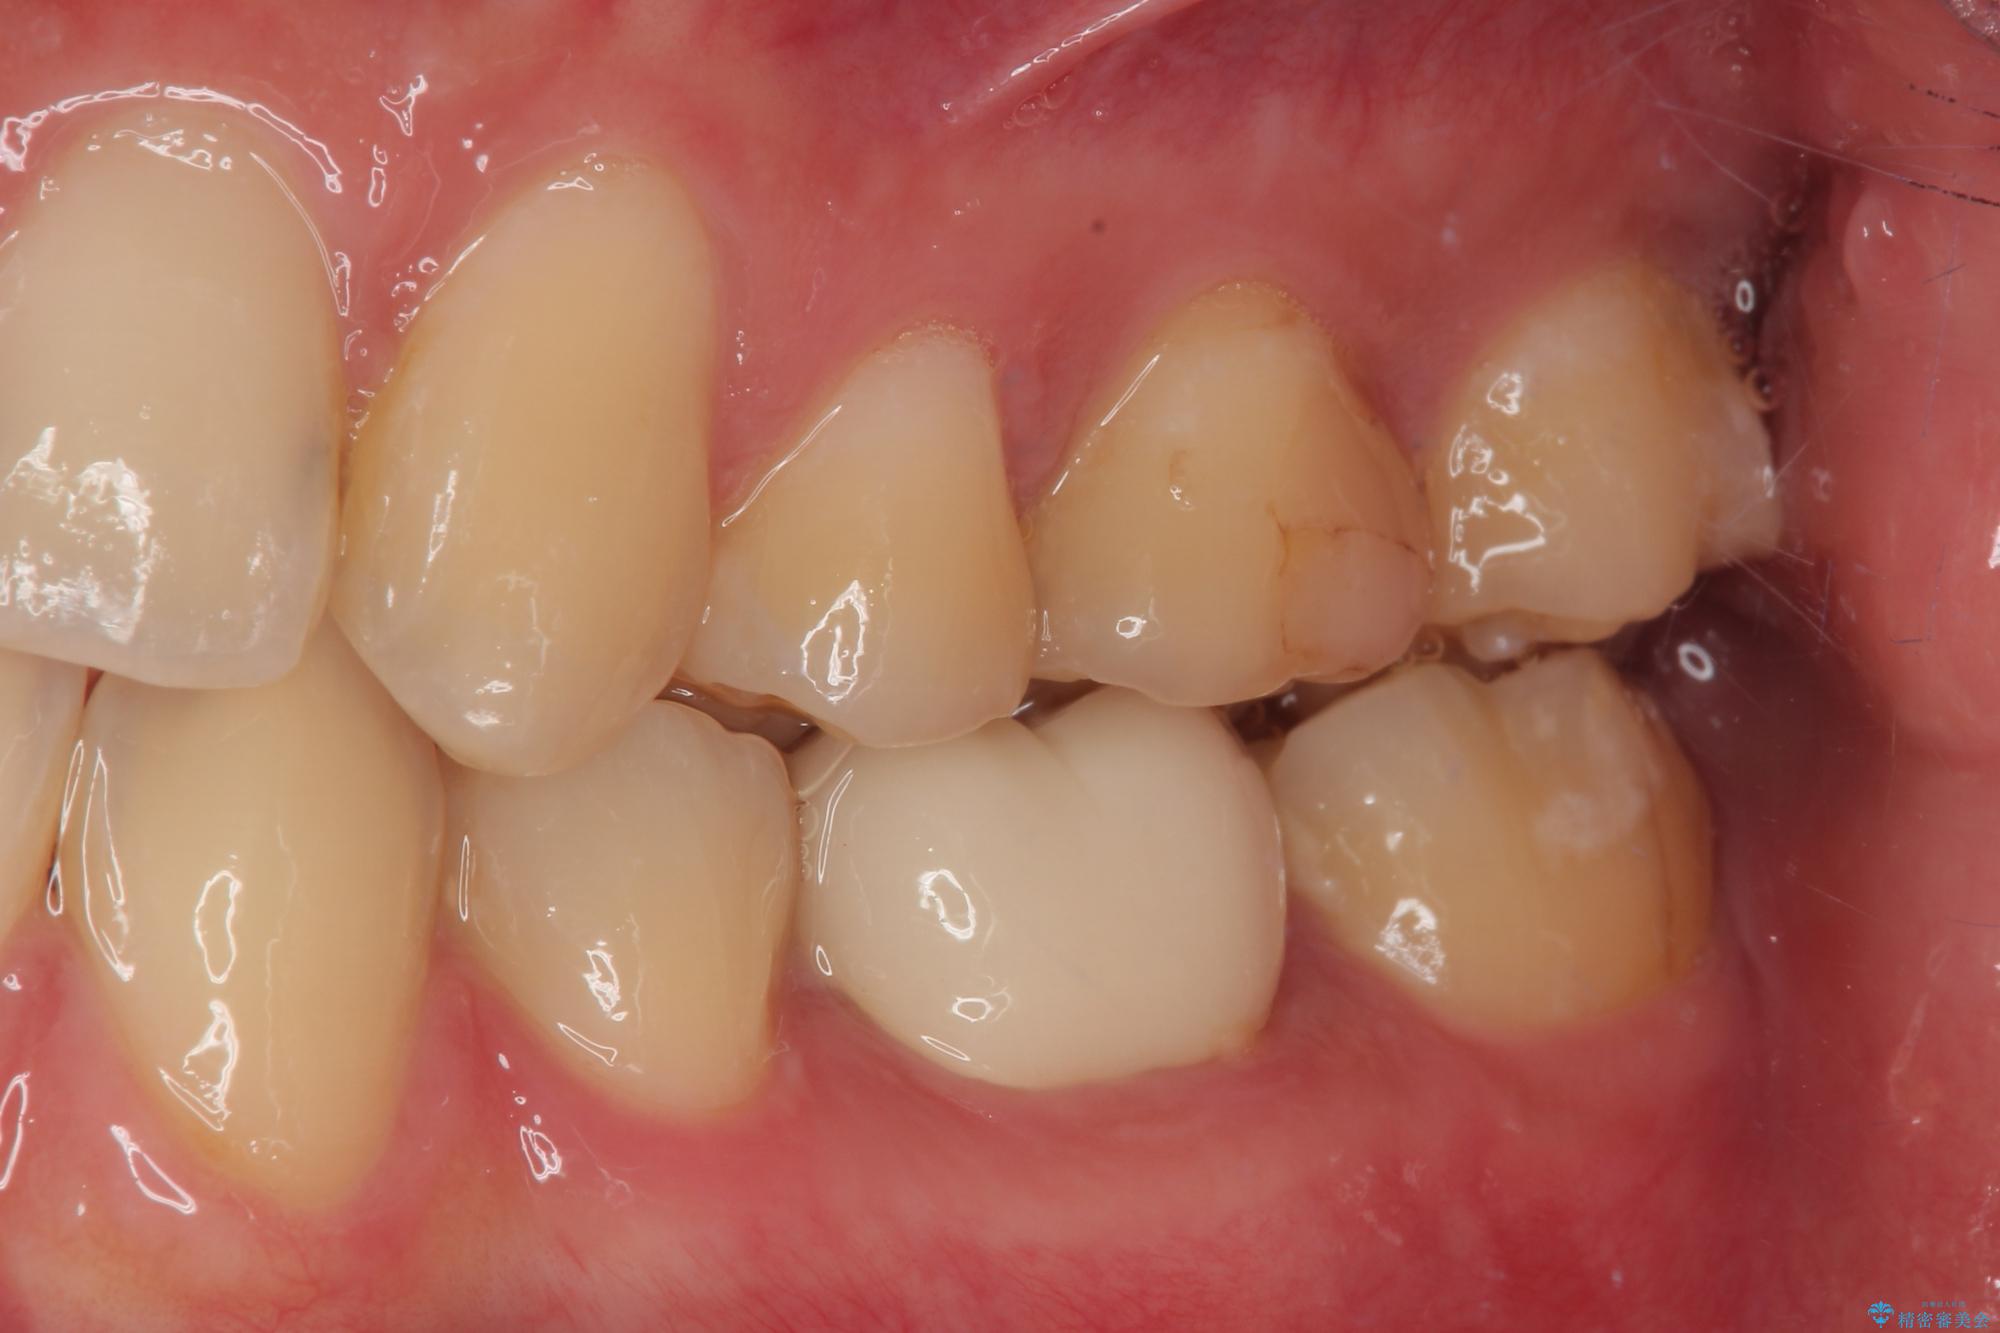

拡大鏡視野下でコンポジットレジン、虫歯の除去を行い、オールセラミッククラウンに適した形に整えました。

歯と歯茎の間に圧排糸と言われる糸を入れてシリコーン印象材にて精密な型どりをしました。